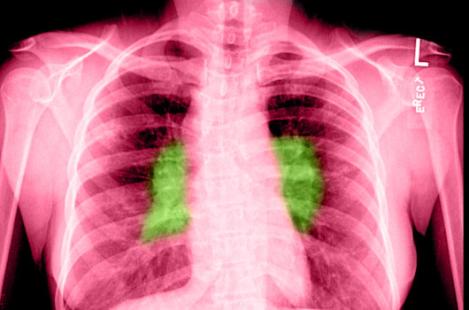

La lévofloxacine a permis de réduire de 60 % le risque de développer une tuberculose multirésistante, selon deux études réalisées indépendamment, mais dont les résultats ont été mis en commun et présentés ensemble lors du Congrès de pneumologie et d'allergologie qui se tient à Paris du 16 au 18 novembre. La première étude a été réalisée en Afrique du Sud auprès d’enfants et la seconde a été effectuée chez des adultes vietnamiens.

Si la tuberculose multirésistante ne représente qu'une petite part du total des cas mondiaux (environ 5 %, soit quelque 450 000 cas), elle est très dangereuse car elle résiste aux deux principaux traitements contre la maladie, l'isoniazide et la rifampicine. Les résultats de ces deux études sont donc intéressants au regard de leur efficacité mais aussi du caractère peu onéreux de la lévofloxacine, fluoroquinolone déjà commercialisée (Tavanic et génériques).